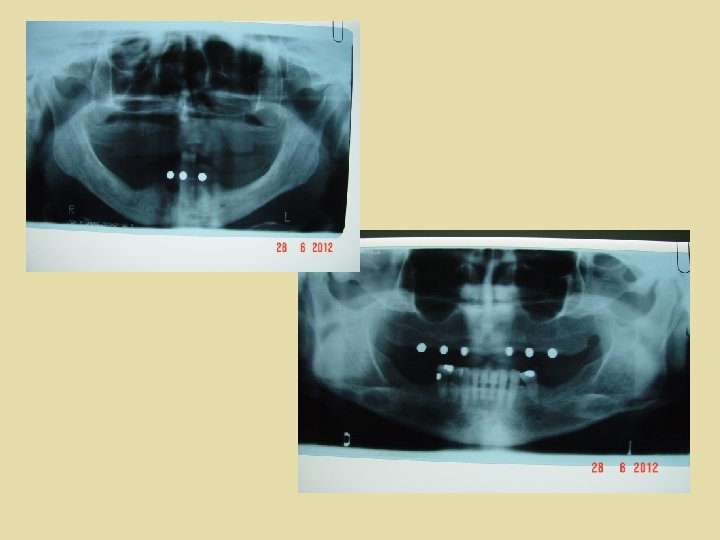

Tipos de férulas radiológicas Férulas construidas con marcadores metálicos de bola Básicamente es una plancha base con uno o varios testigos metálicos con forma de bola y de diámetro conocido, colocados en la zona donde queremos colocar los implantes. Dan poca información y hoy día practicamente no se utilizan. Con este tipo de férula es imposible controlar la angulación del implante.

Tipos de férulas radiológicas Las esferas permiten calcular el error de magnificación y observar si la radiografía panorámica está distorsionada debido a una posición asimétrica de la cabeza en el ortopantomógrafo, en el cual las esferas aparecen de forma ovalada. Se compara el tamaño de las bolitas de la radiografía con la utilizada; con la diferencia de tamaño entre las dos se calcula el factor de distorsión de la radiografía. El error de magnificación, que puede llegar en la vertical a 20 30% de la altura ósea real, debe tenerse en cuenta cuando se evalúe la disponibilidad de hueso en la mandíbula gravemente reabsorbida.